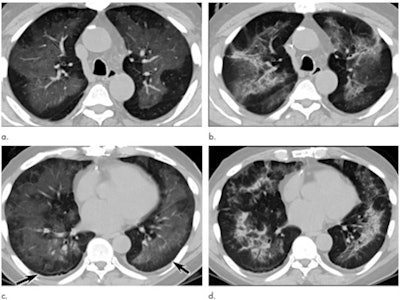

But physicians on the front lines of the pandemic continued to argue that chest CT is a useful tool for initial diagnosis of COVID-19 in some clinical situations, citing the low sensitivity of RT-PCR testing and, therefore, the risk of asymptomatic patients infecting others before their illness develops. In January, Chinese researchers reported on the epidemiological and radiological characteristics of this new virus, describing abnormalities on CT that appeared to be indicative of infection; another group found that chest CT could help clarify negative RT-PCR COVID-19 results.

CT has much to offer for long-term tracking of COVID-19 patients, according to Dr. Seth Kligerman, chief of cardiothoracic imaging at the University of California, San Diego.

"CT is helpful in assessing complications from COVID-19, such as pulmonary thromboembolism," he told AuntMinnie.com. "We are also starting to perform follow-up imaging in patients who had severe lung injury due to [COVID-19] and show variable degrees of lung healing. While the lungs in some patients do appear to nearly completely recover, at least on a macroscopic level, others will wind up with permanent fibrosis, which may lead to debilitation."